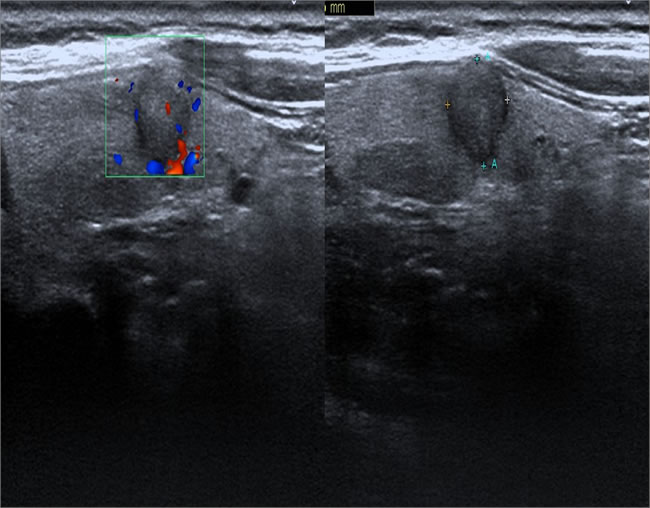

Figure 3: Male patient, 62 years old, sporadic MTC. Lesions showed mixed echogenicity, more cystic components (*).

Specific ultrasound characteristics of 44 MTCs and 119 PTCs are shown in Table 3. Like PTC, MTC showed ultrasonographic features of malignant nodules, including marked hypoechogenicity (37/44, 84.1%), ill-defined margin (28/44, 63.6%), microcalcifications (24/44, 54.5%), and abnormal cervical lymph node (16/35, 45.7%). However, compared with PTC, MTC had significantly larger lesion size (2.10 ± 1.70 cm vs. 0.80 ± 0.70 cm, P < 0.001). Most of the lesions in MTC were oval shaped (Figure 1). The MTC group only had three lesions (3/44, 6.8%) with aspect ratio > 1, which was significantly less than the PTC group (68/119, 57.1%, P < 0.001) (Figure 2). The MTC group had seven lesions (7/44, 15.9%) with a mixed echogenicity (Figures 1 and 3); this was significantly higher than the PTC group (3/119, 2.5%, P = 0.003). The MTC group had 40 lesions with enhanced blood flow signals (40/44, 90.9%) (Figure 4), which was significantly higher than the PTC group (47/119, 39.5%, P < 0.001). Both MTC and PTC groups showed abnormal cervical lymph nodes; the MTC group had 16 cases (16/35, 45.7%) and the PTC group had 32 cases (32/96, 33.3%). The difference between the two groups was not statistically significant (P = 0.21).

Both MTC and PTC groups showed hypoechoic echogenicity in our study. However, five (5/119, 4.2%) lesions in the PTC group showed hyperechoic echogenicity, whereas the MTC group did not have any hyperechoic lesions. These results are consistent with a previous study [15], in which hyperechoic lesions were absent in 157 cases of MTC. Interestingly, we found that the percentage of the mixed echogenicity in MTC and PTC groups was significantly different; 7 of 44 lesions (15.9%) in the MTC group had mixed echogenicity, while 3 of 119 lesions (2.5%) in the PTC group had mixed echogenicity. Some studies [18] have suggested that mixed echogenicity (cystic component > 50%), accompanied with honeycomb change, is an indication of benign nodules. However, our results indicated that the mixed echogenicity of thyroid nodules can also be an ultrasonic feature of MTC.